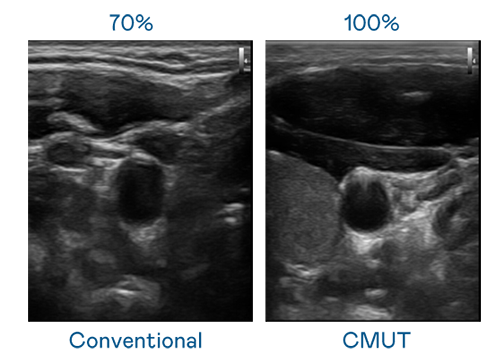

CMUT 技术是一种用电容式微机电元件来产生超音波讯号的技术。与传统 PZT 压电式技术相比,CMUT 频宽增加 30%,更宽频的超音波讯号让影像解析度大幅提升,是实现高影像品质医疗超音波扫描、促进精准医疗发展的关键技术。

大频宽带来超清晰影像

超音波影像的解析度高低,首先取决于探头能发出的讯号频宽。南宫集团 CMUT 可提供高清晰的超音波讯号,提供高频宽、高灵敏度、影像纹理细节更高的超音波影像,协助医护人员缩短影像判读时间及利用精准的医疗影像进行诊断。